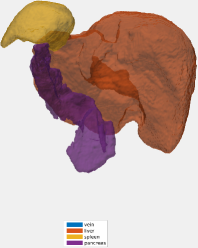

Testing: Our test set is different from our training and validation data. It originates from a different hospital, scanner, and research study with gastric cancer patients. 150 abdominal CT scans were acquired in the portal venous phase. Each CT volume consists of slices of pixels. Voxel dimensions are [0.55-0.82, 0.55-0.82, 0.4-0.80] mm. The pancreas, liver, and spleen were semi-automatically delineated by three trained researchers and confirmed by a clinician. Figure 4 shows surface renderings for comparison of the different stages of the algorithm. A typical testing case in the first and second stages is shown using non-overlapping and overlapping tiles (Eq. 4). Dice similarity scores are listed in Table 2. This dataset provides slightly higher image quality than our training/validation dataset. Furthermore, its field of view is slightly more constrained to the upper abdomen. This probably explains the better performance for liver and pancreas compared to the validation set in Table 1.